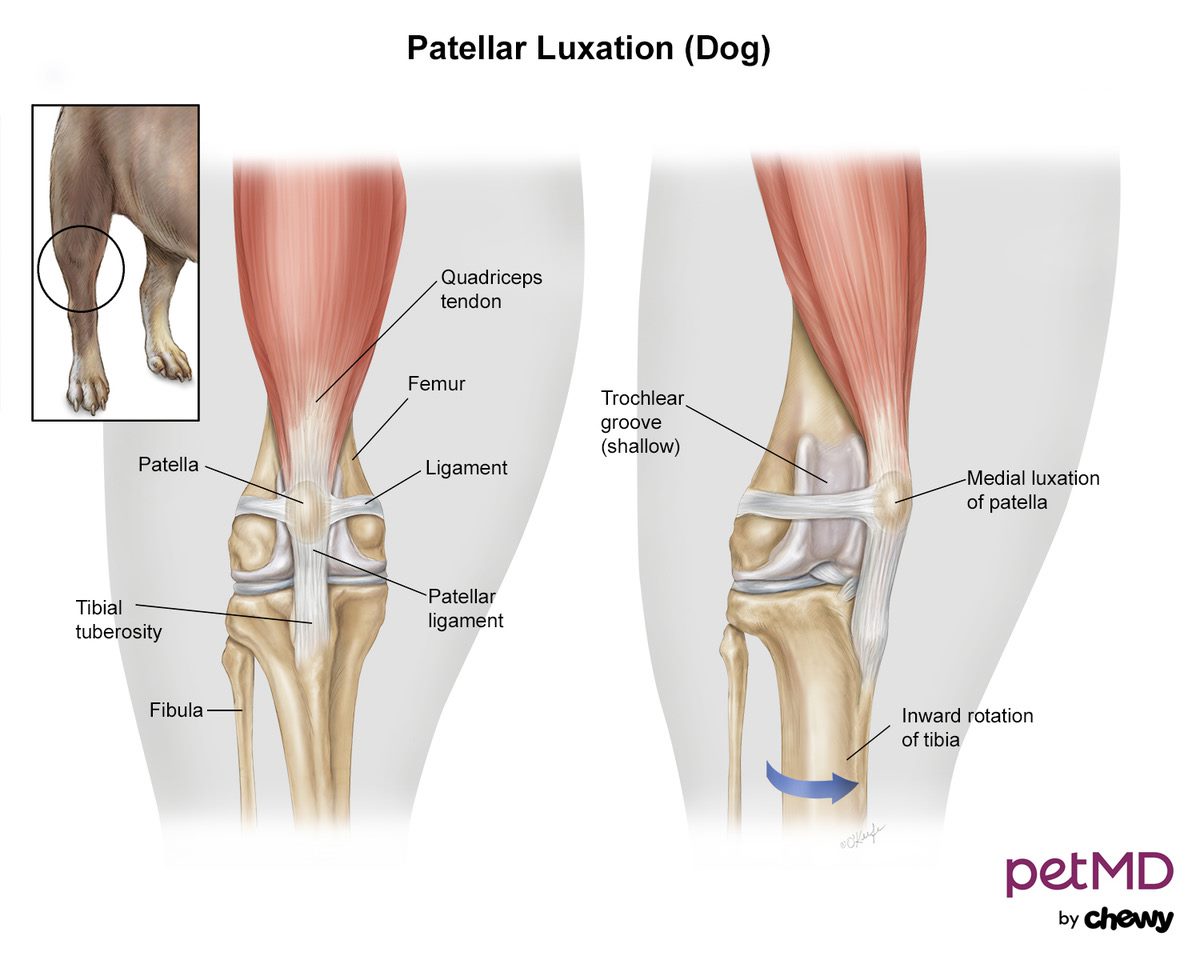

Luxating patella Wikipedia best sale, Floating Knee Physiopedia best sale, Kneecap Instability Medial vs Lateral Patellar Dislocation best sale, Floating Knee Cap recurrent patellar dislocation knee cap Flickr best sale, Floating Knee What Is Floating Knee best sale, Luxating patella in dogs PDSA best sale, Patella Slipping Knee shellylildoggrooming best sale, The Story of the Floating Knees Sanna Dyker best sale, Surgery and non surgical treatments for chronic knee cap best sale, Floating knee A modified Fraser s classification and the results best sale, PDF Bifocal disruption of the knee extensor apparatus best sale, Fraser s classification of floating knee. Download Scientific best sale, Patellar Luxation a Painful Preventable Problem for Small Dogs best sale, Kneecap Instability Medial vs Lateral Patellar Dislocation best sale, Floating Knee Practice Essentials Pathophysiology Etiology best sale, Floating Knee PDF best sale, Patellar Instability Knee Sports Orthobullets best sale, Luxating Patella in Dogs Knee Dislocation Symptoms Causes best sale, Floating Knee Practice Essentials Pathophysiology Etiology best sale, Knee Pain Can Physiotherapy Help The Physio Lounge Blog best sale, Patellar Dislocations Everything You Need To Know Dr. Nabil Ebraheim best sale, Chondromalacia Harvard Health best sale, Kneecap Instability Medial vs Lateral Patellar Dislocation best sale, Frontiers The current issues and challenges in the management of best sale, Patella Kneecap Anatomy and Function best sale, Luxating Patella in Dogs best sale, Floating Knee PDF best sale, Patellar Fractures Broken Kneecap OrthoInfo AAOS best sale, Management of the Floating Knee in Polytrauma Patients best sale, Luxating Patella in Dogs A Complete Guide Dr. Buzby s ToeGrips best sale, Floating Knee Practice Essentials Pathophysiology Etiology best sale, Luxating Patella in Dogs Signs Surgery Cost More Pawlicy Advisor best sale, ii The floating knee in adults and children ScienceDirect best sale, Patellofemoral Instability Kneecap Knee Joint Problems best sale, Patellar Instability symptoms causes best treatment best sale.